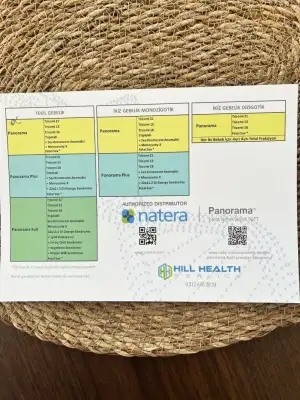

Ben doktorumun önerisiyle panorama test yaptırdım. Amerika’ya gitti kan. 1 haftada geldi sonuç. Başlangıç paketi 425 dolara yaptırdıkKızlar fetal DNA testi yaptırmak istiyorum nerden yaptırıyorsunuz sonuç ne zaman çıkıyor